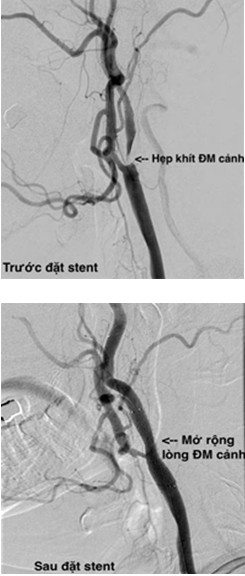

Đặt stent động mạch cảnh (Carotid angioplasty and stenting) là một thủ thuật nhằm mở rộng lòng động mạch cảnh bị hẹp để phòng ngừa hay điều trị đột quỵ. Là phương pháp không Hubet8888 lì xì hội viên mới, đưa dụng cụ qua một lỗ chọc kim ở động mạch đùi (gồm dây dẫn, ống thông gắn bóng, stent) đưa lên vị trí động mạch tổn thương, mở rộng lòng động mạch cảnh bị hẹp, ép mảng vữa xơ vào thành động mạch, tái lập lưu thông dòng máu lên não.

Đặt stent động mạch cảnh Hubet6677 phiên bản mới Hubet Đăng Ký + 8888k nhồi máu não tối cấp hoặc dự phòng nhồi máu não do hẹp động mạch cảnh, đây là một can thiệp nội mạch với ưu thế ít xâm lấn, rút ngắn thời gian nằm viện đã được chứng minh so với phương pháp Hubet8888 lì xì hội viên mới bóc tách nội mạc động mạch cảnh.